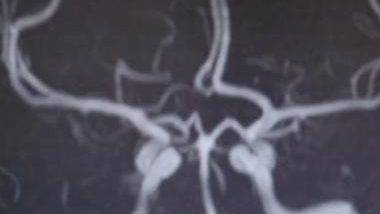

45岁脑梗专家自述“我也脑梗了” 吁警惕这些高危因素

中国上海交通大学附属第九人民医院神经外科主任医生、脑血管专家李轶近日在抖音中自曝,“我今年45岁,我天天治疗脑梗,最后我自己也得了脑梗”,他患的虽属无症状脑梗,但仍令不少网友震惊。